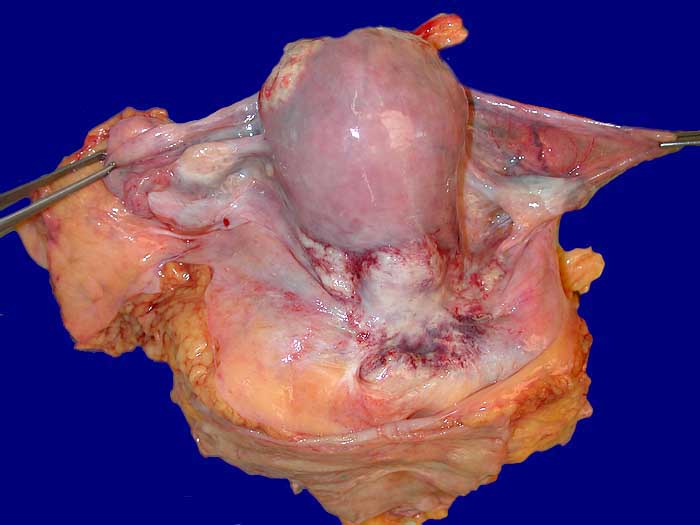

PathoPic – image database / PathoPic ID 6765 - Zervixkarzinom und Endometriumkarzinom

Zervixkarzinom und Endometriumkarzinom

Blick auf den Uterus von dorsal. Das Peritoneum wird im Bereich der Zervix und des Uterusfundus durch stark vaskularisierte Tumoren infiltriert. Tumorfreies Ovar. Tumor im Bereich des Uteruscavum mit Infiltration bis unter die Serosa.

Histologie: endometrioides Karzinom des Cavums und Plattenepithelkarzinom der Zervix.